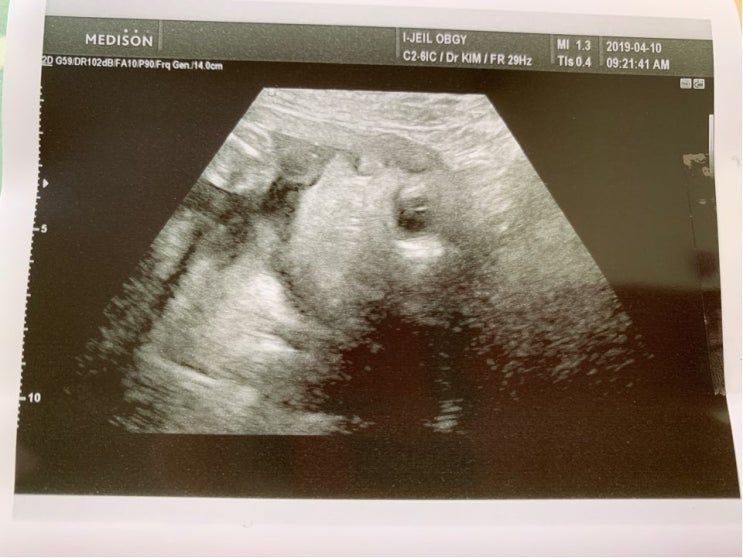

안녕하세요, 정말 오랜만의 블로그인것 같아요. 3일인데 체감상으로는 한 1달지난것 같은.. 임신 32주차에 ...

안녕하세요! 매일매일 #이대맛집 을 서성이는 직장인 임산부 이잦가 입니다. 하하. ㅎㅎ 이제 #육아휴직 이...

오늘로 임신 31주에 들어섰어요! 하하. 아직 실감이 나질 않네요.. 이제 정말 몇주후면 새가족을 맞이 한다...

이제 임신 30주를 지나면서 슬슬 이것저것 자질자질한 육아용품을 사들이기 시작했어요! 저희는 대부분 주...